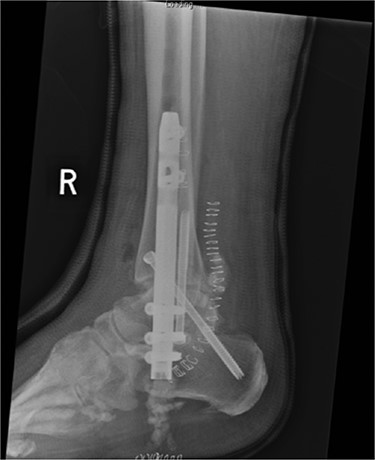

Lateral radiograph of right ankle demonstrating tibiotalocalcaneal fusion using a hindfoot nail and screws.

Preoperatively, radiographs were used to template and to determine the size of the nail. The canal was over reamed by 4 mm: 2 mm of which accommodated for the Cerament mantle, with a further 2 mm to minimise friction during nail insertion. Reamings were sent to microbiology. The canal was washed thoroughly with saline pulsed lavage, gloves were changed and the patient re-draped.

A BIOMET hindfoot nail was attached to its jig and prepared using a single preparation of 10-ml Cerament-V. When in its fluid phase, the Cerament-V was passed through a syringe to cover the nail. The nail was rotated during the setting process such to attain a uniform and smooth surface (Figs 6 and 7). A 14 mm gauge was used to ensure a 2 mm (× 2) thickness of Cerament was achieved. The nail was subsequently inspected such to exclude any defects in the mantle. There was adequate time to ensure that the Cerament had set. Interlocking screw holes were not sited as this may have damaged the cement mould.

The nail was inserted under guidance from fluoroscopy. Proximal and distal locking was performed through the standard jigs (Fig. 8).